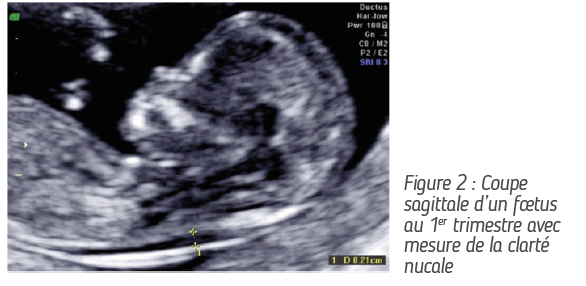

• L’examen du 1er trimestre (+/- 12 SA) peut être combiné au dépistage des anomalies chromosomiques et au dépistage de la prééclampsie (réf. 1, fig. 1 & 2). En Belgique, le dépistage des anomalies chromosomiques comme la trisomie 21 est réalisé via le NIPT (Non Invasive Prenatal Testing). Celui-ci est remboursé depuis juin 2017.